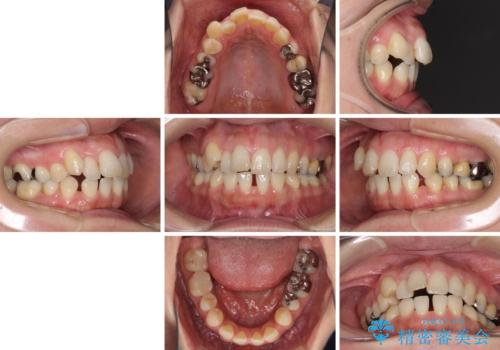

- 八重歯と前歯の隙間を気にして来院された患者様です。

下顎前歯は2本欠損しており、それが原因で隙間ができていました。

また、その影響で上下歯列がアンバランスとなっており、上下前が非接触となっていました。

上下のバランスを取って八重歯などを解消するため、上顎左右第1小臼歯を抜歯することとしました。

根管治療の必要な歯も2本あったため、まずは根管治療を行い、ワイヤー矯正の後に補綴治療を行うこととしました。